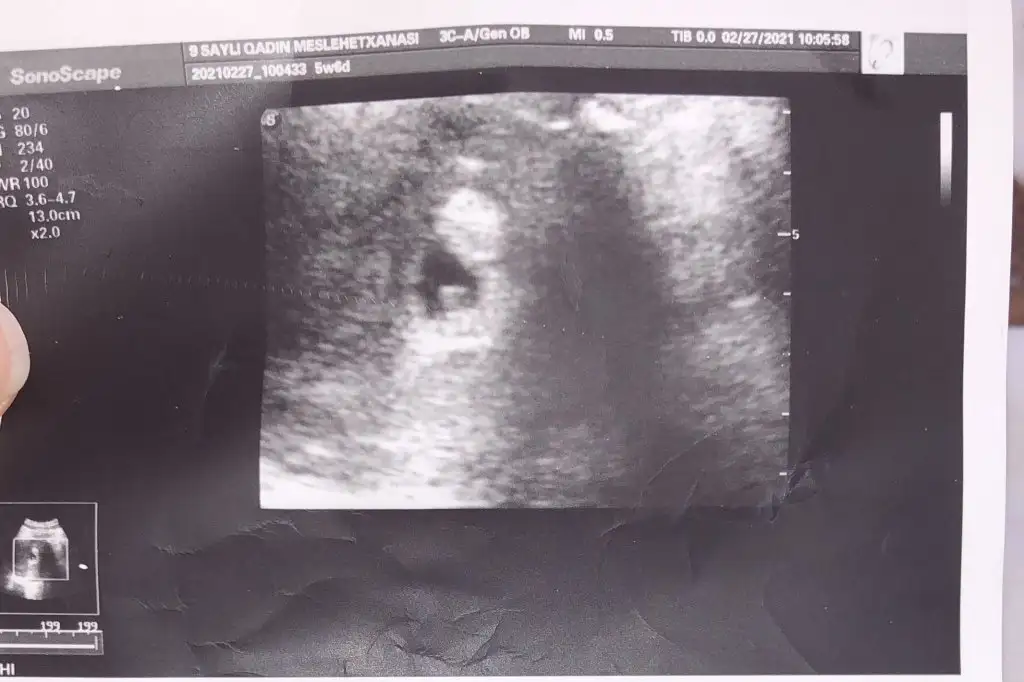

Bide neye göre tahmin yapıyorsunuz sormamda sakınca yoksaDaha çok küçük canım ultrasonda bile görünmüyor en az 3 hafta daha beklemelisin:) erkek olabilir gibi ama sen iki üç hafta sonra yeniden paylaş :) saglikli gebeligin olsun insallah

Buradaki hanımların nub teorisine göre kız gibiEki Görüntüle 2764421 Eki Görüntüle 2764422 Eki Görüntüle 2764423 Tahminde bulunur musunuz arkadaşlar